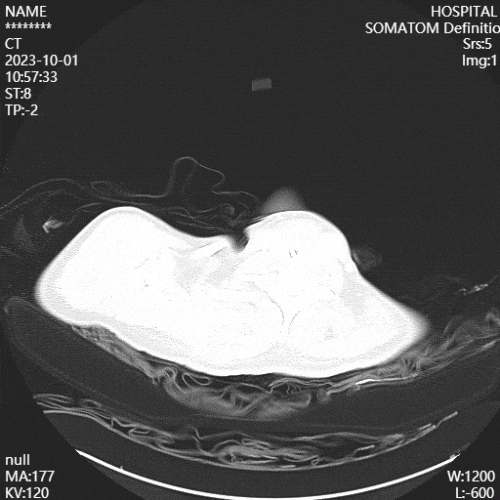

(5)康复措施及效果:复查影像学可见患者肺部炎性病变较前减少。

图片